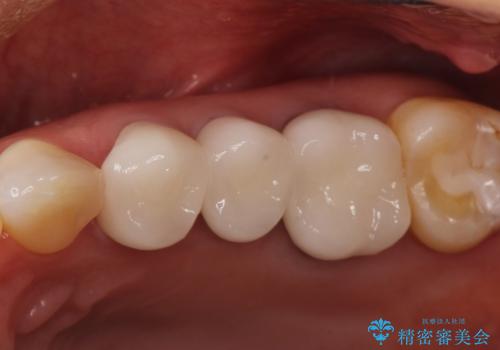

強度に優れたオールセラミッククラウンにて治療を行なっております。

3歯同時に治療を行うこと来院回数は4回で終了しています。